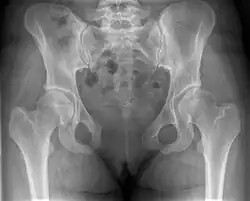

Лобковый симфиз (лобковое сочленение, лонное сочленение, лат. symphysis pubica, от греч. «сращённость»), — расположенное по срединной линии вертикальное соединение верхних ветвей лобковых костей. Располагается спереди от мочевого пузыря и сверху от наружных половых органов (входа во влагалище у женщин и полового члена у мужчин).

Лобковый симфиз — несиновиальное полуподвижное соединение. Ширина симфиза в передних отделах на 3-5 мм превышает его ширину по задней поверхности. Сочленение осуществляется за счёт волокнисто-хрящевого диска, в толще которого часто (у женщин) имеется щелевидная аваскулярная жидкостная полость. Сочленяющиеся поверхности лобковых костей покрыты тонким слоем гиалинового хряща.

Волокнисто-хрящевой диск укреплён врастающими в него связками, способствующими поддержанию стабильности симфиза. Верхняя и нижняя связка более мощные, передняя и задняя менее выражены. Верхняя связка натянута между лонными бугорками и укреплена сухожилиями мышц передней брюшной стенки. Нижняя связка (дугообразная связка, связка Крювелье) расположена вдоль нижнего края лонного сочленения.